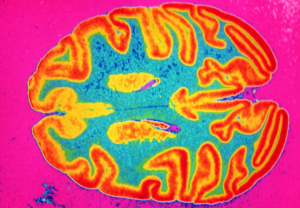

Coronavirus: Bahkan COVID-19 Ringan Dapat Mengecilkan Otak Anda Setara Dengan Penuaan 10 Tahun

Hasil tes COVID-19 yang positif sering kali menimbulkan stres – baik kita sendiri atau orang yang kita sayangi diuji. Namun, orang biasanya merasa lebih baik